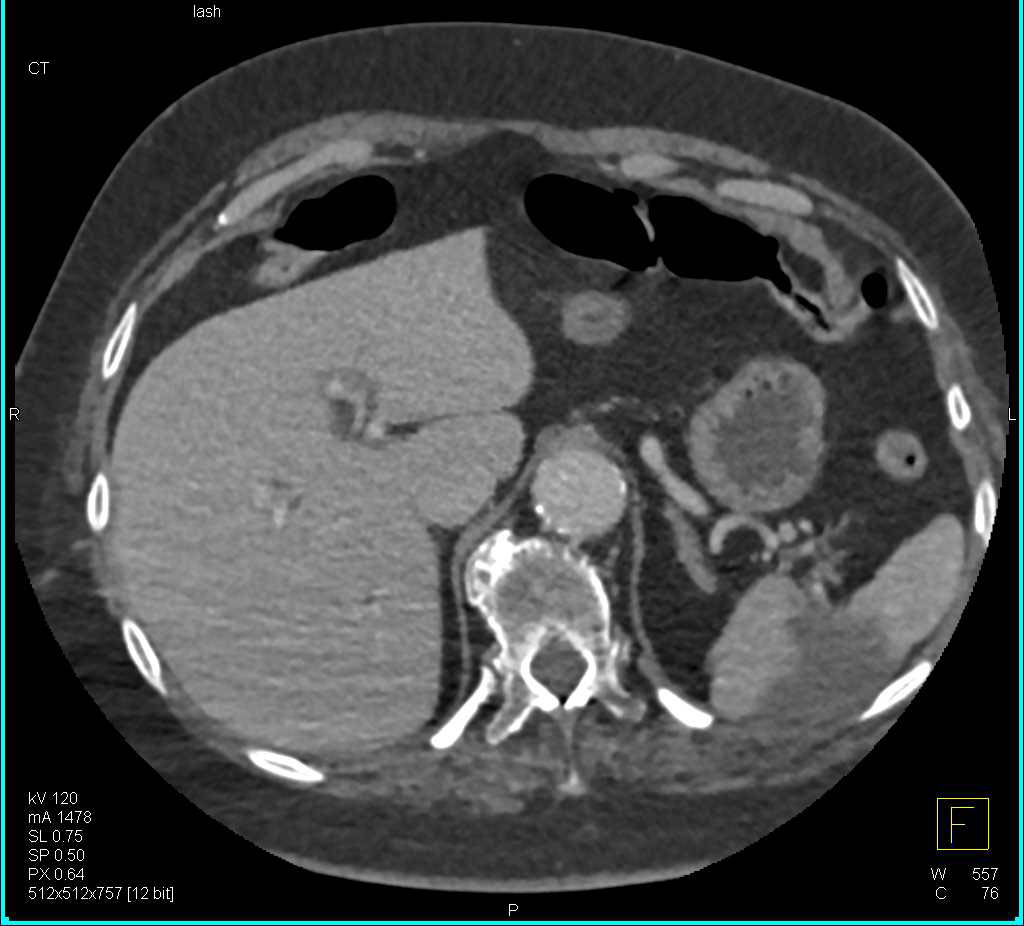

Splenic Hematoma that Has Calcified